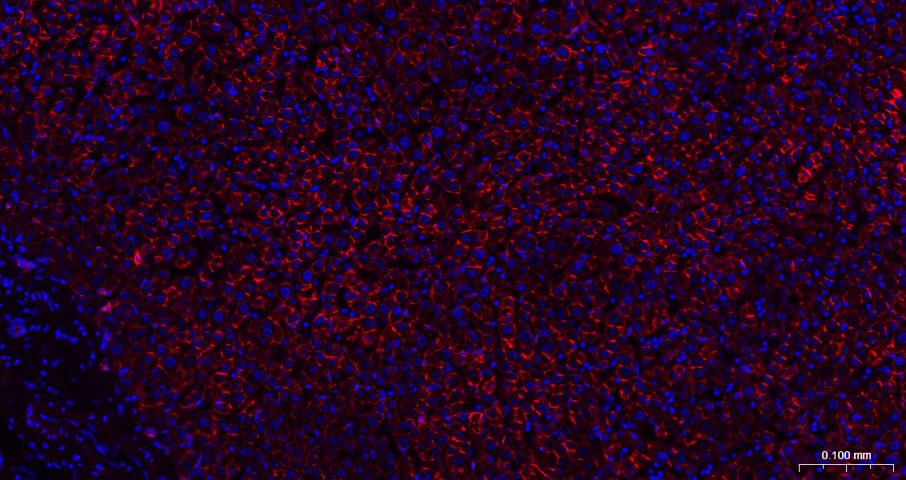

Paraformaldehyde-fixed, paraffin embedded Mouse Liver; Antigen retrieval by boiling in sodium citrate buffer (pH6.0) for 15 min; The section was incubated with N Cadherin Monoclonal Antibody, Unconjugated (bsm-52389R) at 1:200 overnight at 4°C. Followed by conjugated Goat Anti-Rabbit IgG antibody (Red, bs-0295G-BF594), DAPI (blue, C02-04002) was used to stain the cell nuclei.